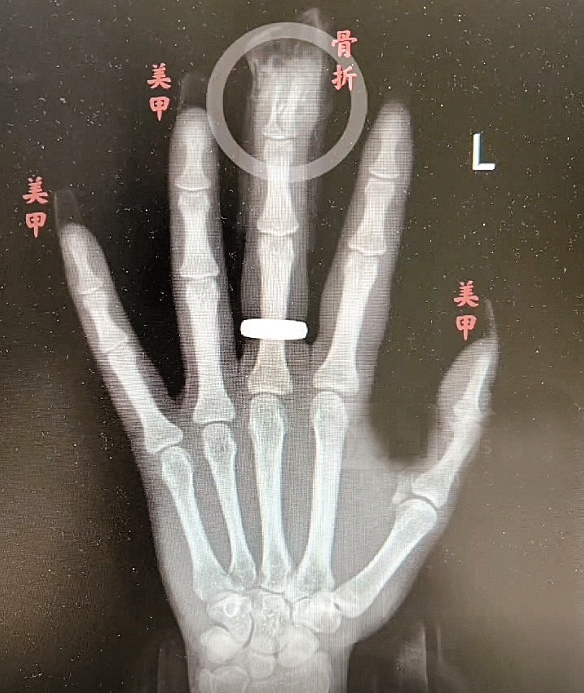

“两根手指末端指骨粉碎性骨折,甲床破裂。”接诊的手外科主任冯伟医生告诉极目新闻记者。相关检查显示,江女士左手中指、环指末端指骨均粉碎性骨折,甲床破裂,其余多根手指软组织挫裂伤。手术中,医生用一根克氏针复位固定了江女士骨折的手指,并用极细的手术缝合线缝合甲床。幸运的是,江女士指尖末端血供不错,术后恢复较好。但由于骨折严重,术后还需要康复锻炼才能争取恢复指尖的屈曲功能,由于甲床受损,半年后重新长出来的指甲可能会没有以前那样平整美观。

对于江女士的伤情,冯伟分析,江女士甲片长度是正常指甲长度的2倍,又有一定向下的弧度,摔倒的瞬间,受到极大冲击力,同时,手指触地时指甲比手掌更早接触地面,再加上甲片被胶水牢牢固定,这时,“甲片就像个杠杆,直接掀翻指甲,导致指骨骨折。”冯伟说,如果没有美甲,伤害远没有现在严重。